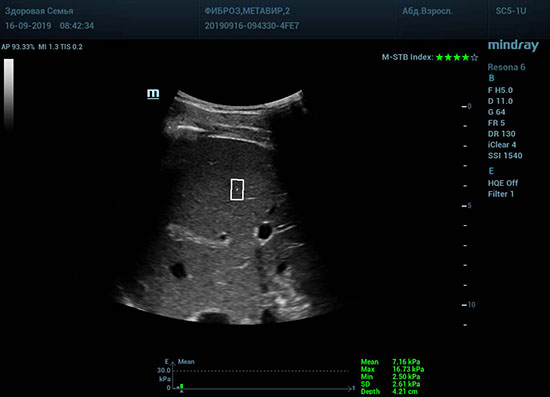

Что может дать ультразвуковое исследование печени помимо образований, гепатомегалии и цирроза? Диагностические системы, оснащенные функцией STQ (SoundTouchQuantification) имеют возможность регистрировать сдвиговые волны в паренхиме печени и оценить её эластичность. Такие возможности есть у систем серии Resona 6 и Resona 7 компании Mindray.

Определение плотности печени. Не ошибся ли оператор при измерении эластических свойств печени? Для оценки критериев качества предусмотрен индекс MBT, который покажет насколько «твердой» была рука оператора и двигалась ли печень. При MBT 5* рука тверда и показатели достоверны. Для оценки качества результатов используется IQR индекс, отображающий колебания показателей в точке измерения при расчете медианы. Показатели при IQR <30% считаются приемлемыми. Техника сканирования через межреберные промежутки требует размещение окна интереса на несколько сантиметром ниже капсулы, для исключения эффекта реверберации. Установка ROI на паренхиму без захвата сосудов, для исключения погрешностей измерения.

Стадия фиброза определяется по системе METAVIR Staging, построенной на данных биопсии и сопоставлении с данными эластографии. Своевременная диагностика фиброза, и начало его лечения, залог благоприятного исхода заболевания.